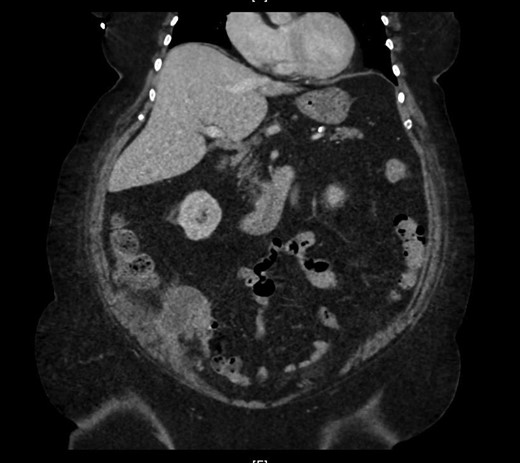

CT scan of the abdomen revealed stable soft tissue focus and adjacent rim of enhancing low-density collection along the posteromedial and posterior aspects of the cecum in the right lower abdomen (Fig. 2). Suggestive of the possibility of chronic infectious or neoplastic etiologies of appendicular origin. The appendix was not visualized as a separate structure. Comparison of the previous CT excluded worsening of the intra-abdominal or intra-pelvic process. Upon discussion with medical and surgical teams, reproduction of symptoms and CT evidence, aided the direction for surgical intervention. On the second day of hospital admission, surgical laparoscopy located the terminal ileum with adhesions from the sidewall. The findings included perforated viscus and mass at the appendicular base. With this appearance, a direct intervention was impossible, we proceeded with hand-assisted partial cecectomy, appendectomy and removed the entire mass.

Marked appendiceal wall swelling and intraluminal filling defect of contrast medium over appendix noted in the coronal CT-image.